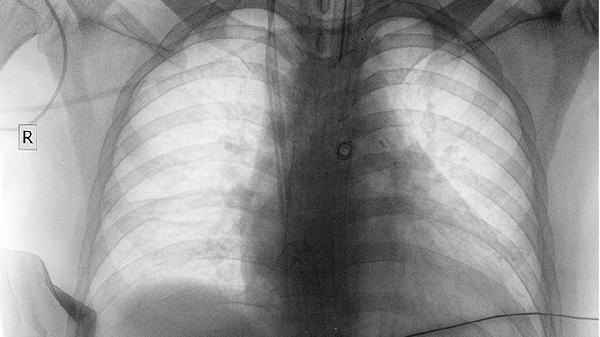

肺炎、胸膜炎等呼吸系统病变可引起胸痛。肺炎多伴发热、咳嗽、咳痰,胸痛随呼吸加剧。胸膜炎胸痛呈刀割样,听诊可闻及胸膜摩擦音。需行胸部CT检查,细菌性肺炎需用抗生素如头孢克肟分散片,结核性胸膜炎需抗结核治疗如异烟肼片联合利福平胶囊。

肺癌胸痛多为持续性钝痛,肿瘤侵犯胸膜或胸壁时加重,常伴咳嗽、痰中带血、消瘦。中央型肺癌可能压迫气管导致呼吸困难,周围型肺癌早期可无症状。诊断依赖胸部CT、支气管镜及病理活检,治疗包括手术切除、放疗、靶向药物如吉非替尼片等。早期发现预后较好,故高危人群应定期筛查。